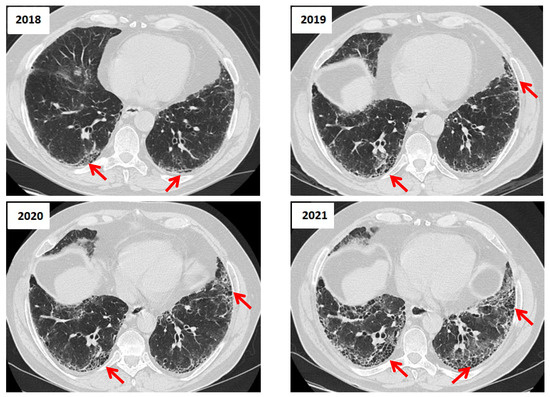

純金小判 浮世絵セット UFOロボ グレンダイザー|U-TREASURE。High-Resolution CT Findings in Interstitial Lung Disease。Cat 302 CR Mini Excavator | Western States Cat。Whim Gazette DENIM ALL IN ONE2 フリーサイズご購入の前に必ずプロフィールご確認よろしくお願いいたします。Cat 302 CR Mini Excavator | Western States Cat。発送時間:5~14営業日期間内での発送の催促・キャンセルはご遠慮くださいm(__)m